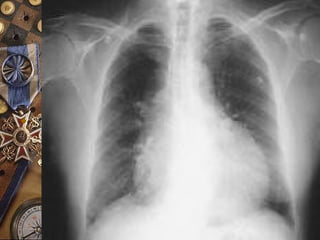

DERRAME PERICARDICODERRAME PERICARDICO

 Importante determinar tiempo de evolución por riesgo de

taponamiento cardíaco.

 Disminución de la intensidad de los ruidos cardiacos,

ruidos cardíacos hipofonéticos, desaparece el frote, se

desplaza choque de punta

 Disminución de la intensidad del pulso apical

 Signo de Ewart : zona de matidez por debajo del ángulo

de la escápula izquierda.

 Ortopnea, tos y disfagia